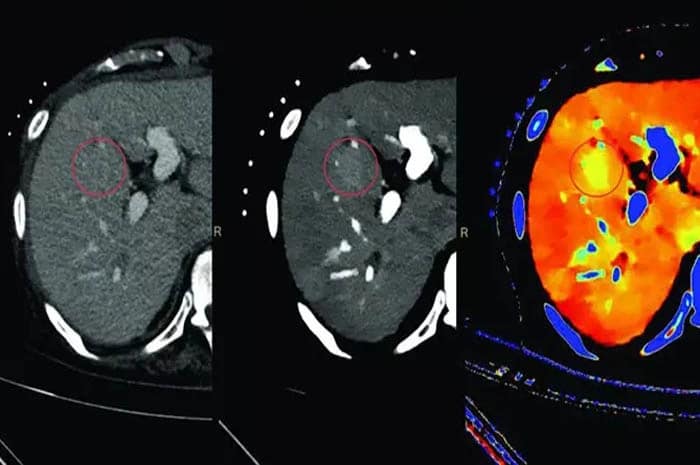

رادیوگرافی رنگی چیست؟

رادیوگرافی رنگی | راهنمای جامع و کامل رادیوگرافی رنگی یکی از روشهای تخصصی تصویربرداری پزشکی است که در آن از ماده حاجب (Contrast Agent) برای وضوح بیشتر تصاویر استفاده میشود. این ماده به پزشکان کمک میکند اندامها، رگها و بافتهای داخلی بدن را بهتر ببینند و بیماریها با دقت بیشتری تشخیص داده شوند. تفاوت رادیوگرافی […]